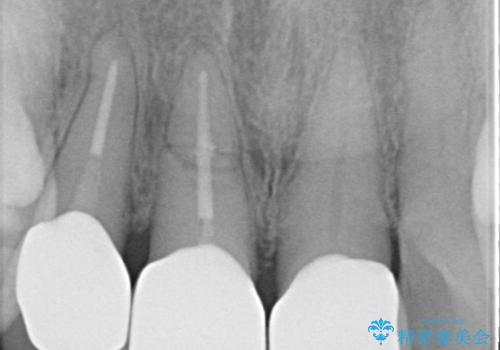

【外傷歯】根管治療から被せ物まで。

- 外傷により他院で治療中に転院を希望され受診されました。

前医では、抜歯も提案をされていましたが適切に治療を行うことで歯を保存することができました。

歯槽骨内水平性歯根破折は、抜歯の適応ではありません。